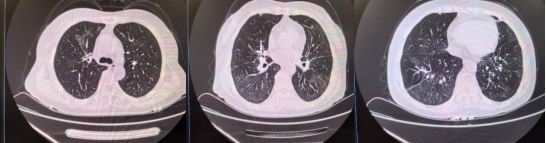

1个月后复查胸部CT

明确病因后,戚刚强主任团队开展有针对性的治疗,时刻关注患者病情变化。在医护人员的悉心照护下,患者病情逐渐稳定,症状消失,复查胸部CT显示较前明显吸收,治疗有效。